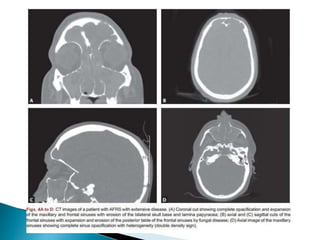

 CT usually shows homogeneous opacification of

the affected sinus(es), iso-to hyperattenuating to

muscle tissue.

 Other suggestive features include:

◦ relative lack of expansion of sinuses 2

◦ mottled lucencies or irregular bone destruction may be

seen

◦ bone erosion localized to the area of extrasinus

extension 2

◦ extrasinus component of the disease more prominent

than the intrasinus component 2

◦ there may also be sclerotic changes in the bony walls of

the affected sinuses representing chronic disease